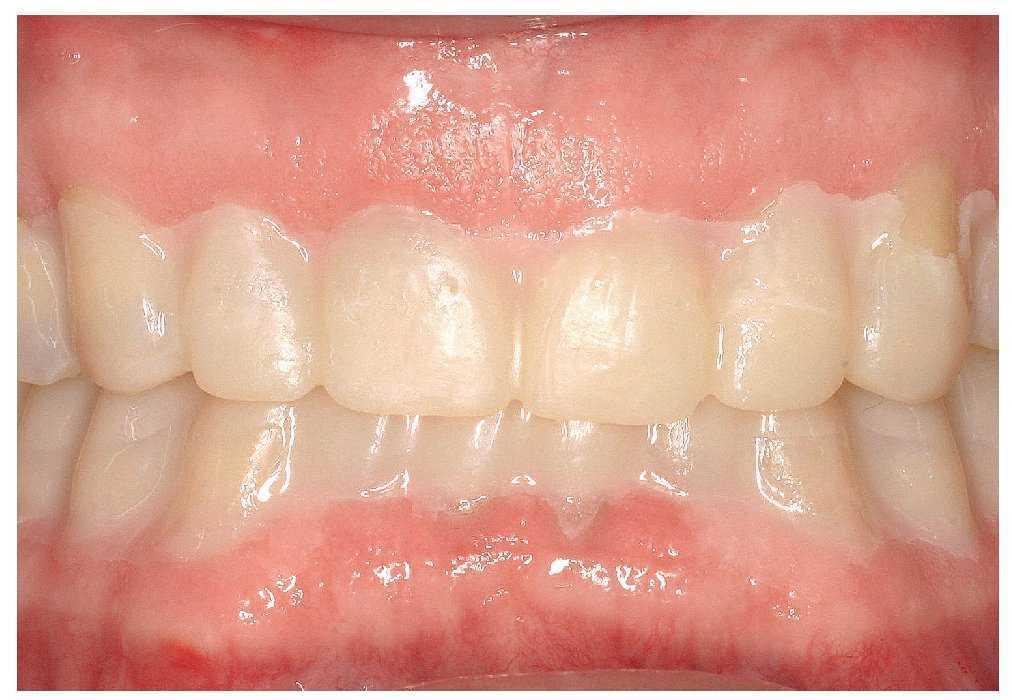

Después de controlar intraoralmente el ajuste, la estética y la función se prepararon las restauraciones para el cementado. Las caras internas de las restauraciones fueron chorreadas cuidadosamente (óxido de aluminio de 50 μm, Pluradent, Offenbach) a una presión de 2 bar65 y los restos de cemento provisional fueron eliminados de las superficies preparadas con copas de profilaxis (copas Prophy, Hager & Werken, Duisburgo, Alemania) sin pasta. Bajo un aislamiento relativo del campo llevado a cabo con aislantes de saliva (dry tips, Mölnlycke Health Care, Erkrath) y rollitos de algodón (rollos de algodón Luna de Roeko), se cementaron todas las restauraciones (figs. 18, 21 y 22) sin realizar un grabado ácido previo de la sustancia dentaria y utilizando un cemento de composite de polimerización dual autoacondicionador (Ralyx Unicem, 3M Espe). Una vez retirado el exceso de cemento se realizó un nuevo control intraoral de la oclusión.

Figura 21. Vista oclusal de la arcada superior con las restauraciones cementadas.

Figura 22. Restauraciones en la arcada inferior.